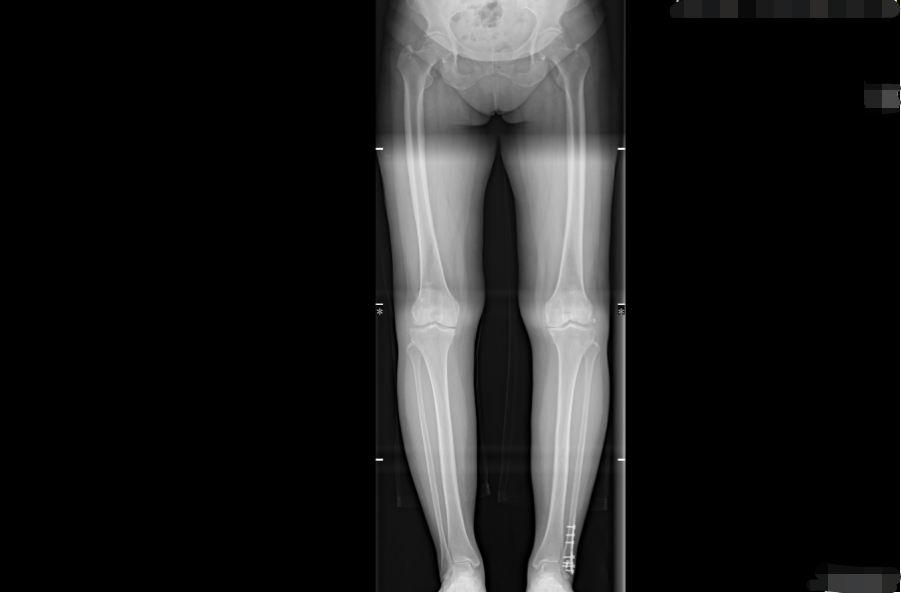

经胡舒主任详细检查与评估,冯阿姨被诊断为重度膝关节骨性关节炎。由于保守治疗效果不佳,为彻底解决疼痛、恢复关节功能,胡主任建议进行膝关节置换术。在充分沟通和了解了自己的疾病及治疗方式后,冯阿姨选择在家门口的东凤人民医院手术治疗。

(术前) (术后)